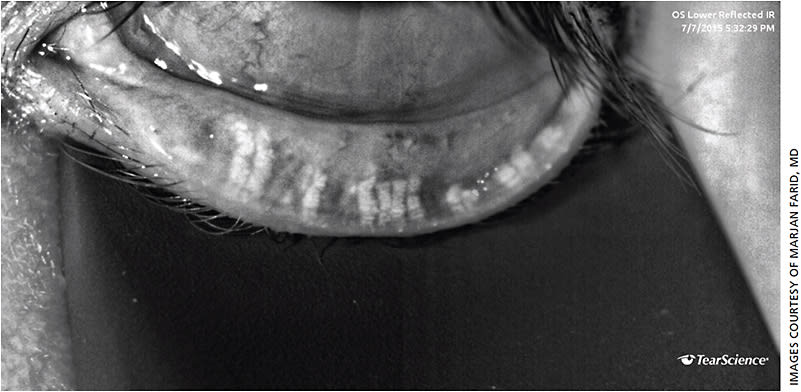

Useful tools for showing patients the physical signs of their pathology include meibography imaging of the meibomian gland architecture (Figure 1) and slit lamp photos of cornea fluorescein staining. Side-by-side photo comparisons of the patient’s photos to “normal” and severely “abnormal” can validate their symptoms and could even motivate some patients to adhere to a treatment plan, especially those who are asymptomatic but have moderate to severe signs of DED. Allowing the patient’s accompanying family member to look through the slit lamp oculars (on low magnification) to see the “dry spots” also makes the disease more tangible and encourages increased compliance with treatment. Another useful visual includes measuring the tear meniscus height with anterior segment OCT.